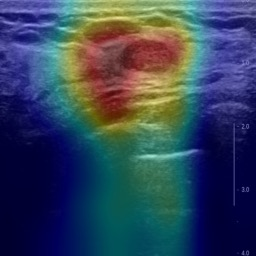

Ultrasonography is an important routine examination for breast cancer diagnosis, due to its non-invasive, radiation-free and low-cost properties. However, it is still not the first-line screening test for breast cancer due to its inherent limitations. It would be a tremendous success if we can precisely diagnose breast cancer by breast ultrasound images (BUS). Many learning-based computer-aided diagnostic methods have been proposed to achieve breast cancer diagnosis/lesion classification. However, most of them require a pre-define ROI and then classify the lesion inside the ROI. Conventional classification backbones, such as VGG16 and ResNet50, can achieve promising classification results with no ROI requirement. But these models lack interpretability, thus restricting their use in clinical practice. In this study, we propose a novel ROI-free model for breast cancer diagnosis in ultrasound images with interpretable feature representations. We leverage the anatomical prior knowledge that malignant and benign tumors have different spatial relationships between different tissue layers, and propose a HoVer-Transformer to formulate this prior knowledge. The proposed HoVer-Trans block extracts the inter- and intra-layer spatial information horizontally and vertically. We conduct and release an open dataset GDPH&GYFYY for breast cancer diagnosis in BUS. The proposed model is evaluated in three datasets by comparing with four CNN-based models and two vision transformer models via a five-fold cross validation. It achieves state-of-the-art classification performance with the best model interpretability.